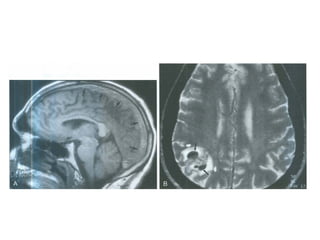

VENOUS INFARCTS

Venous infarcts in brief

Venous drainage

Venous territories

Deep veins

Venous thrombi

• Dural sinus thrombosis

• Cortical venous thrombosis

• Deep cerebral venous thrombosis

• Thrombus initially forms in dural sinus

• Clot propagates into cortical veins

• Venous drainage obstructed, venous pressure

elevated

• Blood-brain barrier breakdown with vasogenic

edema, hemorrhage

• Venous infarct with cytotoxic edema ensues

Venous ischemia

• Type 1: No abnormality

• Type 2: High signal on T2WI/FLAIR; no

enhancement

• Type 3: High signal on T2WI/FLAIR;

enhancement present

• Type 4: Hemorrhage or venous infarction

Empty delta sign

Cord sign